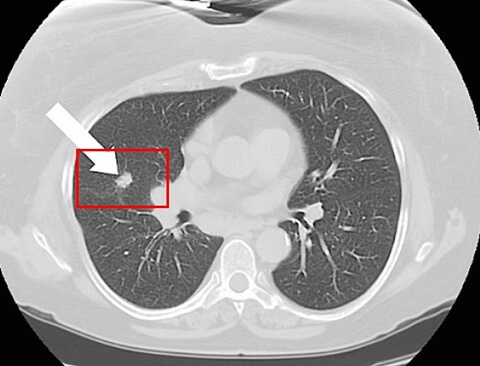

그리고 최소한은 검진이라도 국가에서 해주는 저희가 국가검진이 아주 잘 돼 있다고 하는데, 엑스레이나 저소량 시티 같은 그런 국가검진이라도 꾸준하게 이제 잘 챙겨서 잘 받으시고

✔ 초기 증상은 거의 없으나, 기침, 각혈, 가래 변화, 통증, 호흡곤란, 체중 감소 등으로 나타날 수 있습니다.

✔ 증상이 경미하더라도 검진을 통해 조기 발견이 중요하며, 금연과 정기 건강검진이 예방의 핵심입니다.